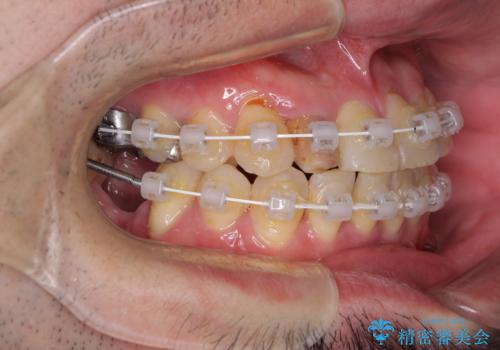

咬み合わせは受け口傾向であり、上顎前歯の叢生が顕著であったことから、第1小臼歯抜歯による矯正治療も検討しましたが、下顎大臼歯を左右ともに抜歯するため、非抜歯による矯正治療を行うこととしました。

矯正治療でインプラント埋入を行い、矯正治療後に気になる前歯と合わせてオールセラミッククラウンによる補綴治療を行うこととしました。